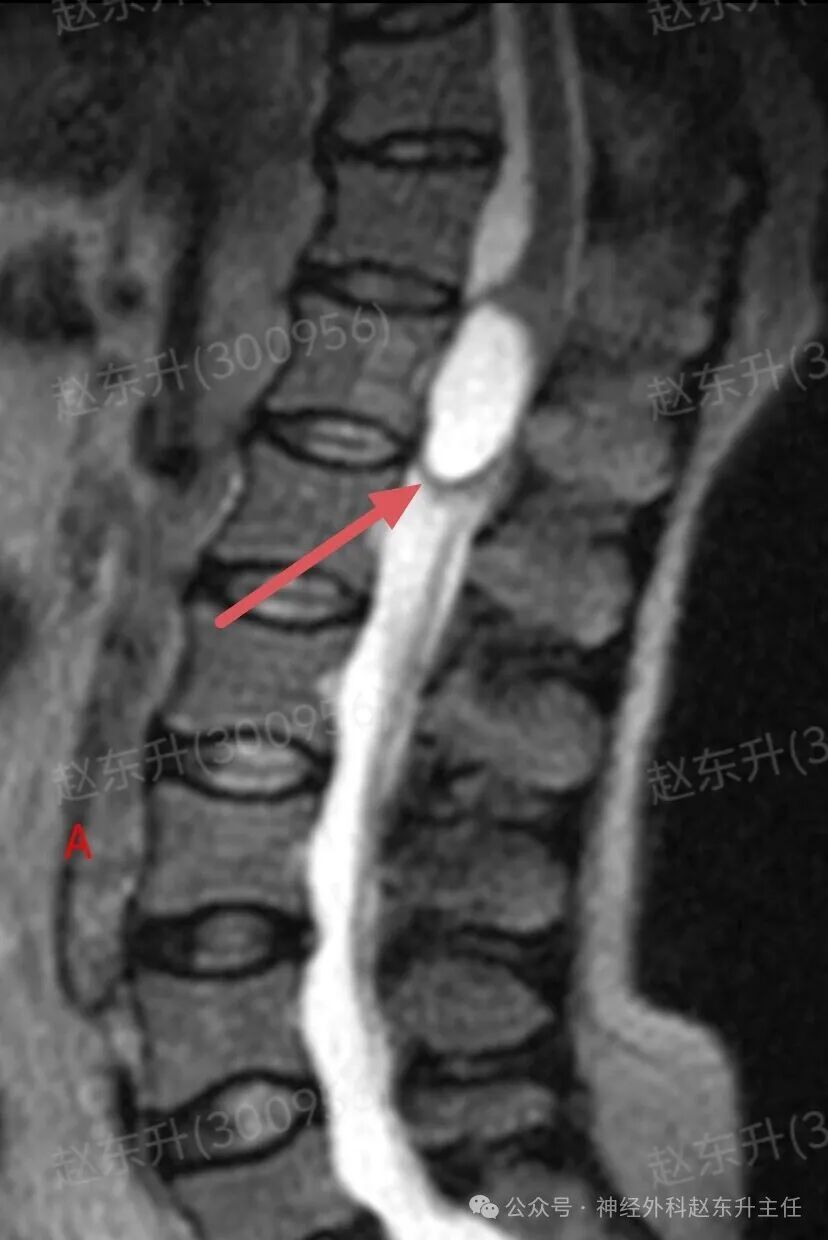

上周门诊来了一位58岁女性,患者因为下肢和腰背部顽固性疼痛半年,在各大医院就诊曾行针灸按摩,艾灸电疗等治疗没见缓解,而且疼痛评分可以达到8-9分,口服止痛药无效,康复理疗无效。随后查了一下腰椎磁共振,发现胸12腰1节段脊髓内异常信号,随后收入我科。入院之后查肌电图提示下肢和骶神经损伤严重,随后我们在全麻下使用显微镜,并且术中电生理监测下,给予脊髓内肿瘤次全切除,术后病理提示是胶质瘤。术后第2天我们就给他用了经颅磁刺激等神经康复治疗,虽然术后第1天右下肢肌力较术前减退,但经过10天的治疗以后,下肢肌力逐渐恢复,可以下地行走了。术后他还需要进一步的放疗和化疗来抑制肿瘤的生长,预防肿瘤复发。

图片图片图片图片图片图片图片图片切除的肿瘤图片术后病理西安市红会医院神经外科赵东升主任介绍:脊髓内胶质瘤是一种起源于脊髓实质内部的胶质细胞(即神经系统的“支持”细胞)的肿瘤。与脊膜瘤(位于脊髓外)的关键区别在于,它生长在脊髓内部,因此会浸润并破坏正常的脊髓神经组织核心特征:性质:涵盖从低级别良性到高级别恶性的完整谱系,但以低级别为主。位置:完全位于脊髓中央,可累及多个脊髓节段,甚至全长脊髓。特点:肿瘤与正常脊髓组织边界不清(浸润性生长),手术全切极为困难。其生长直接破坏神经传导束,导致严重神经功能障碍。发病率:相对少见,约占所有中枢神经系统胶质瘤的2-4%,但却是儿童最常见的髓内肿瘤。无明显性别差异。与脊膜瘤的关键区别总结

主要类型1.室管膜瘤(约占60%):常见的成人髓内胶质瘤。多为低级别(WHO I级和II级),生长缓慢。常发生于颈段和胸段,常有明确边界,有时可有“假包膜”,是手术全切希望最大的一种。2.星形细胞瘤(约占30%):常见的儿童髓内胶质瘤。从低级别(毛细胞型星形细胞瘤,WHO I级,预后好)到高级别(胶质母细胞瘤,WHO IV级,预后极差)都有。浸润性生长为特点,与正常脊髓几乎无边界,手术全切风险极高。3.其他少见类型:如血管母细胞瘤(常与VHL病相关)、少突胶质细胞瘤等。临床表现(症状)症状因肿瘤生长缓慢而隐匿、渐进性加重,早期易被忽视。典型症状:1.感觉障碍(最早、最常见):l分离性感觉障碍:这是特征性表现。由于肿瘤侵犯脊髓中央的白质前连合,导致痛觉、温觉纤维受损,而触觉、深感觉保留。患者表现为双侧对称性的、节段性的痛温觉减退或消失,而触觉正常l麻木、酸痛、束带感。2.运动障碍:n肿瘤平面以下出现肢体无力、僵硬、肌肉萎缩(尤以手部小肌肉萎缩常见)。n行走困难,步态不稳。3.疼痛:定位不明确的颈背部疼痛,夜间痛可能更明显。4.自主神经功能障碍(晚期):l大小便失禁或困难。l性功能障碍。l皮肤营养障碍(无汗、皮肤干燥等)。诊断增强磁共振(MRI): 是首选和确诊的关键检查。典型表现:可见脊髓呈梭形、偏心性或中心性增粗。肿瘤在T1像呈等或低信号,T2像呈高信号,增强后强化模式多样(可均匀、不均匀或环形强化)。可清晰显示肿瘤范围、有无囊变、脊髓空洞等。CT:价值有限,主要用于评估是否有脊椎骨质改变。治疗治疗远比脊膜瘤复杂,需在多学科团队(神经外科、肿瘤科、放疗科)指导下进行个体化综合治疗手术治疗(首要且核心):l目标:在最大限度保护神经功能的前提下,实现最大安全程度的肿瘤切除。全切是目标,但常因肿瘤边界不清而无法实现。l技术:在术中神经电生理监测(监测运动、感觉传导束功能)的保驾护航下,使用显微外科技术、超声吸引、激光等进行精细操作。功能保护优先于肿瘤全切放射治疗:主要适用于:高级别胶质瘤术后辅助治疗、无法全切的低级别胶质瘤术后残留、肿瘤复发无法再次手术者。化学治疗:l对于高级别(恶性)脊髓胶质瘤,可参照脑胶质瘤方案进行化疗(如替莫唑胺)。l对于部分复发的低级别胶质瘤也可能使用。预后与随访预后差异巨大,高度依赖于肿瘤的病理类型和分级l低级别室管膜瘤:若能实现全切,预后良好,可达到长期无进展生存,甚至临床治愈。复发率低。l低级别星形细胞瘤(如毛细胞型):全切后预后也很好。次全切后也可能长期稳定。l高级别胶质瘤(如胶质母细胞瘤)预后极差,即使积极治疗,也极易在脊髓内播散复发,生存期短。l随访:术后需定期(通常每3-6个月,后逐渐延长)进行增强MRI复查,监测肿瘤是否残留或复发。神经功能康复治疗至关重要赵东升主任简介医学硕士,西安市红会医院北院区神经外科主任医师,从事神经外科近20年。使用独创的“三维一体疗法”成功促醒大量昏迷病人,使上百例脊髓损伤瘫痪患者重新站起来。最早在陕西省开展第一例脊髓电刺激治疗昏迷病人,第一例脊髓电刺激手术治疗截瘫病人,第一例脊髓电刺激手术治疗下肢缺血顽固性疼痛。主编专著3部,参编专著11部,发表学术论文30余篇,荣获国家专利32项(其中四项发明专利),担任多部杂志编委及审稿专家。擅长:1.脑病方面:昏迷促醒,脑肿瘤、脑积水、脑梗死偏瘫、肌张力增高、顽固性癫痫、三叉神经痛、脑干出血、老年痴呆、帕金森、头痛等;2.脊髓病方面:脊髓损伤、脊柱术后疼痛、大小便障碍、脊髓肿瘤、脊髓空洞、小脑扁桃体下疝畸形、脊髓栓系、脊膜膨出、痉挛性截瘫等;3.周围神经疾病方面:糖尿病足、下肢缺血性疼痛、臂丛神经损伤、腓总神经损伤、腕管综合征、肘管综合征、男性功能障碍等门诊时间:北院区:周一全天门诊二楼203A  第五诊室南院区:周二全天门诊三楼310诊室